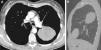

We report the case of a young asymptomatic patient with a chest mass that was finally diagnosed as an intrafissural primitive neuroectodermal tumor (PNET). A pulmonary mass was detected in this 27-year-old woman on an unrelated chest X-ray. All laboratory test results were normal. Computed tomography (CT) revealed an elliptic, heterogeneous mass with contrast uptake in the left hemothorax, about 12cm in diameter with smooth borders, located within the oblique fissure of the left pleura (Fig. 1). CT-guided fine-needle aspiration biopsy cytology was inconclusive. Surgical resection revealed an intrafissural mass. Hematoxylin and eosin staining produced a surprisingly uniform pattern of solidly compacted round cells.

The most common CT finding in PNET is a mass with heterogeneous contrast uptake. Occasionally, a central area of low density with no contrast uptake seen inside the mass. The heterogeneous aspect of these large tumors is usually due to focal areas of bleeding or necrosis.5